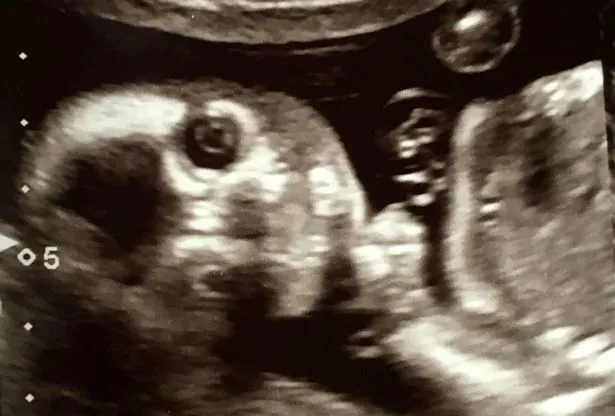

A várandóssága 20. hetében járó Jo szíve szerint kimenekült volna a szobából, amikor meglátta a születendő gyermekéről készült ultrahangfelvételt – írja a Daily Star.

Ez mondjuk nem is annyira meglepő! A magzat ugyanis pont belenézett az endoszkópba, mintha tisztában lett volna azzal, hogy róla készül a felvétel.